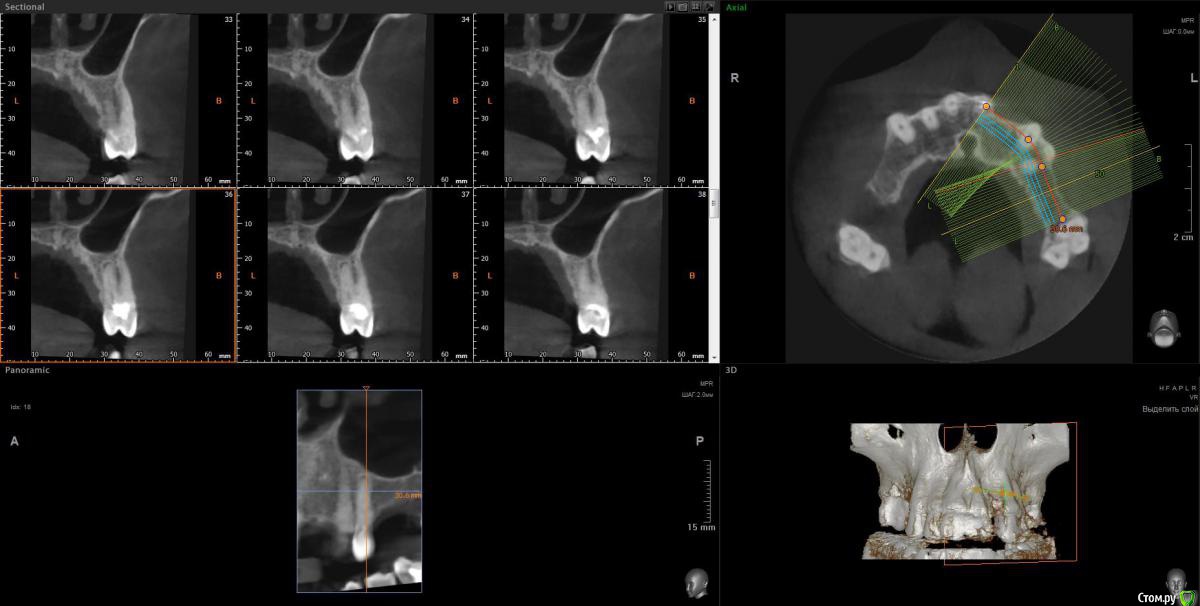

Просьба ко всем не равнодушным! Глянуть КТ верхней челюсти, 27 зуб  и место где удалили 16, может ещё где-то могут быть проблемы.  На фото видно где покраснение на дёснах, в этих местах возникают боли при движении головой. Бывает боль слева если засыпаю на левой стороне. Набуханий или флюсов нигде не видно.Прошу делиться мнениями, для меня это очень - очень важно. Стоматолог визуальных проблем на месте удалённого зуба не видит, всё зажило.

температура иногда бывает 37.2. ну чувствую себя как будто 38.5.по общему анализу крови было без особых отклонений. Может ли после удаления зуба долго идти  не заметный вялотекущий воспалительный процесс в десне?  Может 27 является источником инфекции? Там на снимке видна скрытая полость.

По данным КТ в зоне удалённого зуба 16 ничего особенного, разве что, ретенированный (непрорезавшийся) зуб 18.

Зуб 27 требует внимания, необходим очный осмотр.

Также стоит обратить внимание на зубы 21 и 24